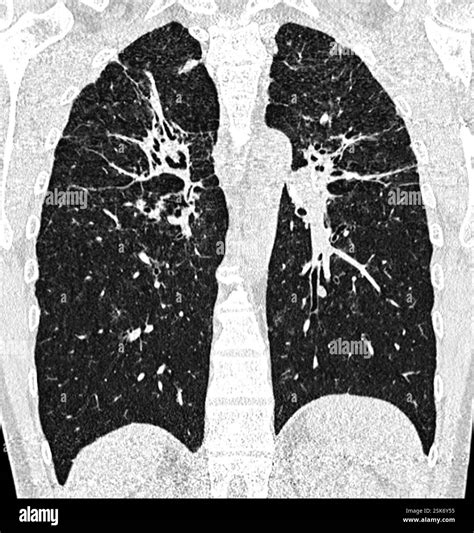

Receiving medical imaging results can often feel overwhelming, especially when terms like lung scarring on CT scan appear on your radiology report. Finding evidence of scarring—medically referred to as pulmonary fibrosis or interstitial lung abnormalities—can trigger anxiety, but it is important to remember that these findings are descriptive and require clinical context to be fully understood. A CT scan is a highly sensitive diagnostic tool that provides a detailed cross-sectional view of the lungs, allowing doctors to identify changes in the lung tissue that might not be visible on a standard chest X-ray. Understanding what this scarring means, why it happens, and what steps you should take next is the first step toward managing your respiratory health effectively.

When a radiologist identifies lung scarring on CT scan, they are typically referring to the presence of fibrotic tissue. In a healthy lung, the tissue is delicate, thin, and elastic, allowing it to expand and contract effortlessly with every breath. When injury occurs, the body attempts to repair the tissue; however, in certain conditions, this repair process goes awry, leading to the buildup of excess connective tissue.

This scarred or thickened tissue is less flexible than healthy lung tissue. Over time, as this scarring accumulates, it can make the lungs stiff, making it more difficult for oxygen to pass from the air sacs (alveoli) into the bloodstream. This physiological change is what leads to symptoms such as shortness of breath and a persistent, dry cough.